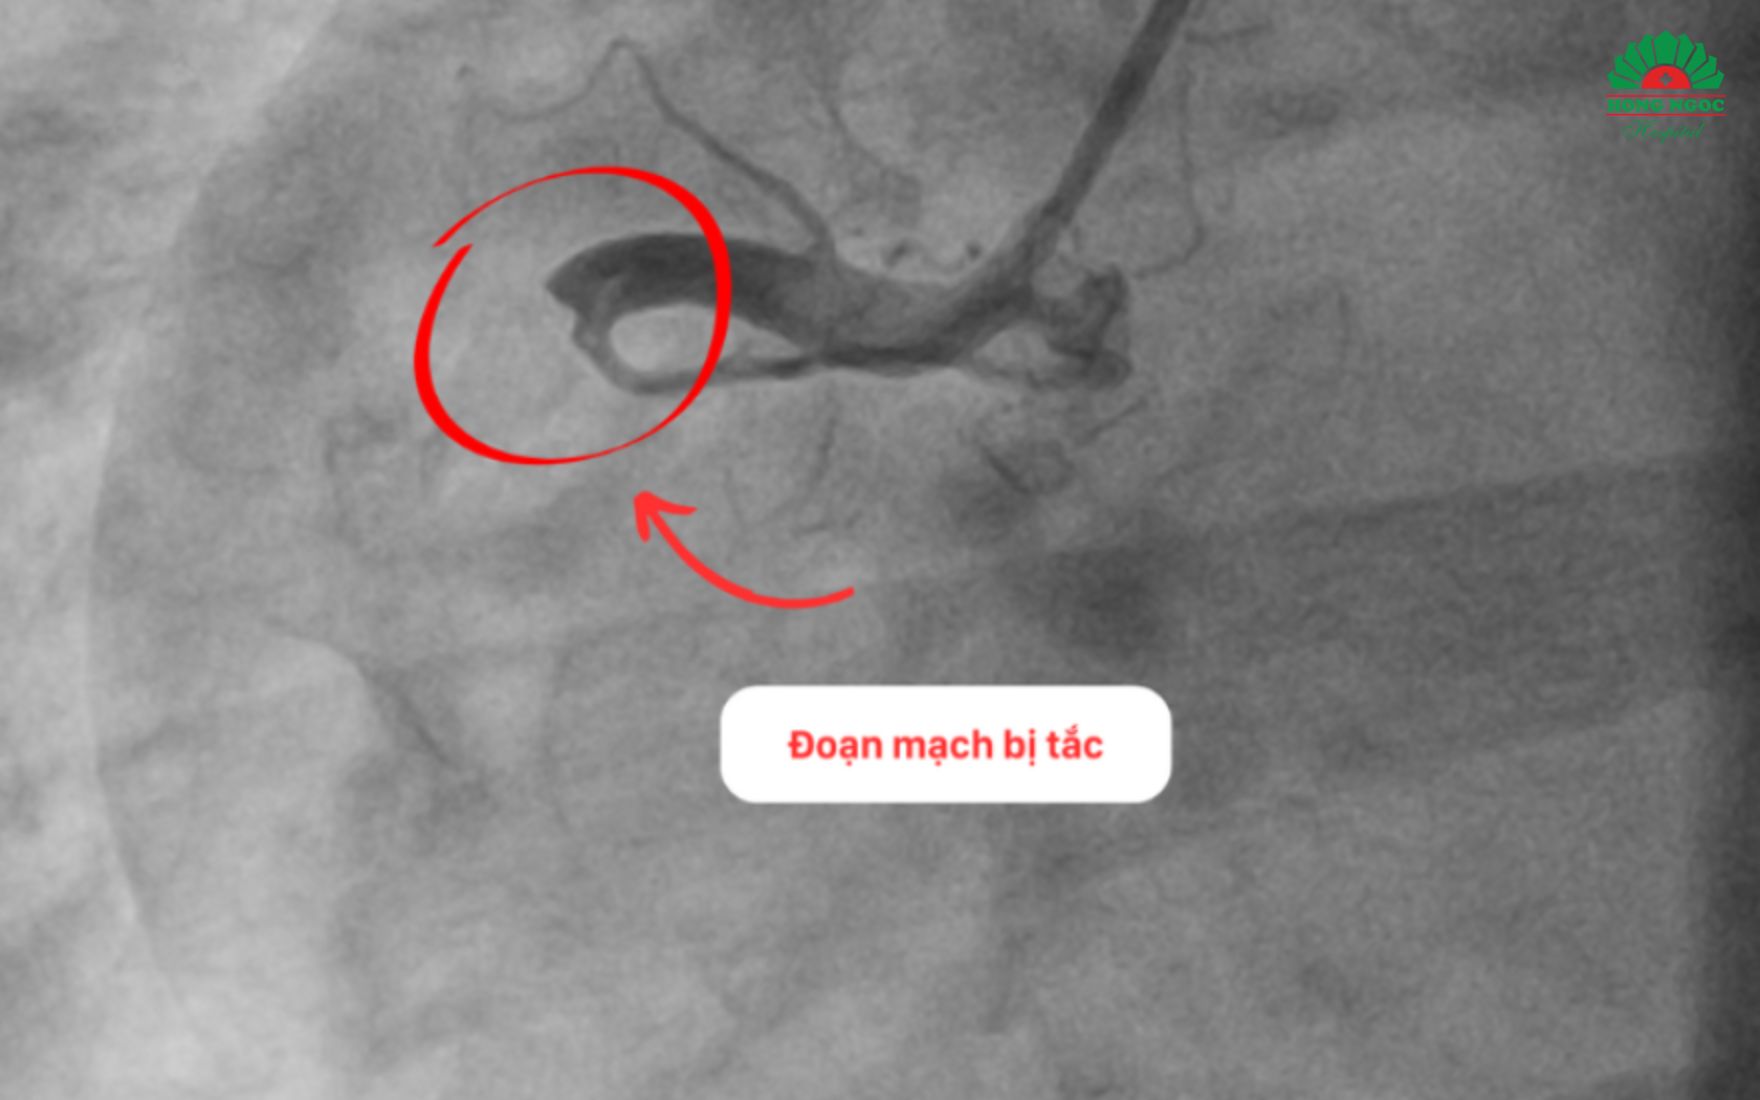

Ngay lập tức, ông Sơn được chuyển lên phòng can thiệp tim mạch. Kết quả chụp mạch vành cho thấy lượng huyết khối lớn gây tắc hoàn toàn tại đoạn I của động mạch vành phải. Đây là một trong ba động mạch quan trọng cung cấp máu nuôi tim cho bệnh nhân.

Huyết khối gây tắc hoàn toàn động mạch vành phải